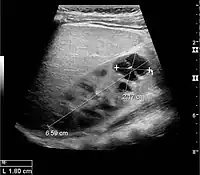

The hydronephrosis is typically graded visually and can be divided into five categories going from a slight expansion of the renal pelvis to end-stage hydronephrosis with cortical thinning (Figure 15). The evaluation of hydronephrosis can also include measures of calyces at the level of the neck in the longitudinal scan plane, of the dilated renal pelvis in the transverse scan plane and the cortical thickness, as explained previously (Figure 16 and Figure 17).[1]

Figure 18. Renal stone located at the pyeloureteric junction with accompanying hydronephrosis.[1]

With US, larger stones (>5–7 mm) within the kidney, i.e., in the calyces, the pelvis and the pyeloureteric junction, can be differentiated, especially in the cases with accompanying hydronephrosis (Figure 18 and Figure 19). Hyperechoic stones are seen with accompanying posterior shadowing. Additional twinkling artifacts below the stone can often be seen using Doppler US. Large stones filling the entire collecting system are called coral stones or staghorn calculi and are easily visualized with US (Figure 20). Stones in the ureters are usually not visualized with US due to the air-filled intestines obscuring the insonation window. However, ureteral stones near the ostium can be visualized with a scan position over the bladder. An exam of the ureteric orifices and the excretion of urine to the bladder can be performed by inspecting the ureteric jets in the bladder with color Doppler US.